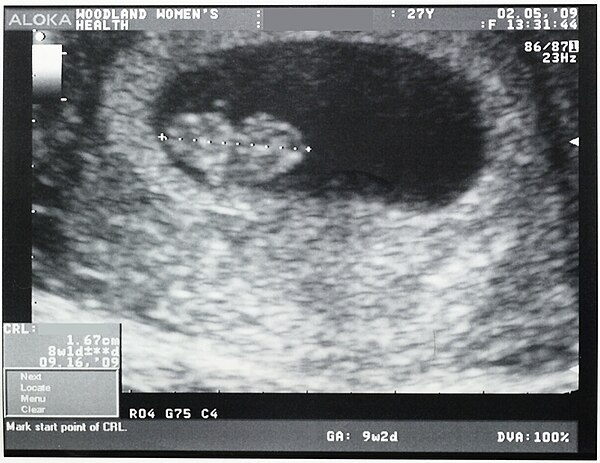

Чтобы точно установить диагноз «замершая беременность», врач может отправить беременную на ультразвуковое исследование. Это наиболее подходящий вариант,

чтобы точно определить патологию. если срок слишком маленький, то исследование проводится повторно спустя неделю.

- На ультразвуковом исследовании не слышно плодного сердцебиения, а показатели размеров матки не соответствуют сроку беременности.

Важно! Если до 7-й недели имеются подозрения на замершую беременность, то аборт откладывают до повторного ультразвукового исследования. Может случиться так, что аппарат не обнаружил жизненных функций эмбриона или врачом была допущена ошибка при расчетах сроков зачатия.

- ранний срок — неправильное расположение плодного яйца или его повреждение;

- поздний срок — отсутствие сердцебиения у плода и несоответствие его размеров сроку.

Данных УЗИ недостаточно для постановки окончательного диагноза — ЗБ. Из-за гормональных сбоев и психологических нагрузок у женщин задержка развития плода может составлять до четырех недель. В этом случае проводят повторное УЗИ через две недели. Если плод не увеличился в размерах, то это означает, что он мертв.

Показания УЗИ — это самый надёжный и достоверный показатель, подтверждающий наличие замершей беременности. Ошибки случаются только на ранних сроках беременности, когда врач может принять за пустое плодное яйцо, нормально развивающееся. В таком случае, если состояние пациентки не внушает опасений, можно подождать до 6-7 недель и повторить УЗИ. На этом сроке опытный врач при помощи современной аппаратуры уже хорошо видит эмбрион и слышит его сердцебиение.

- Ультразвуковое исследование, с помощью которого врач определяет сердцебиение плода, наличие или отсутствие живого эмбриона. Если сердцебиение не прослушивается на сроке до 8 недель – это ненадежный показатель гибели эмбриона.

Рекомендуется провести повторное УЗИ через неделю. - Лабораторное исследование крови для определения уровня ХГЧ (хорионического гонадотропина человека). При значительном снижении ХГЧ можно с большой долей вероятности утверждать, что беременность не развивается.

Такой диагноз можно поставить после прохождения УЗИ .

По УЗИ не определяется сердцебиение и шевеление плода. Эмбрион по размерам меньше, чем должен быть. Может выявляться пустое плодное яйцо (анэмбриония). На УЗИ женщина может быть направлена при подозрении на замершую беременность, либо это может быть выявлено при плановом проведении УЗИ (срок первого планового УЗИ – 10–14 недель).